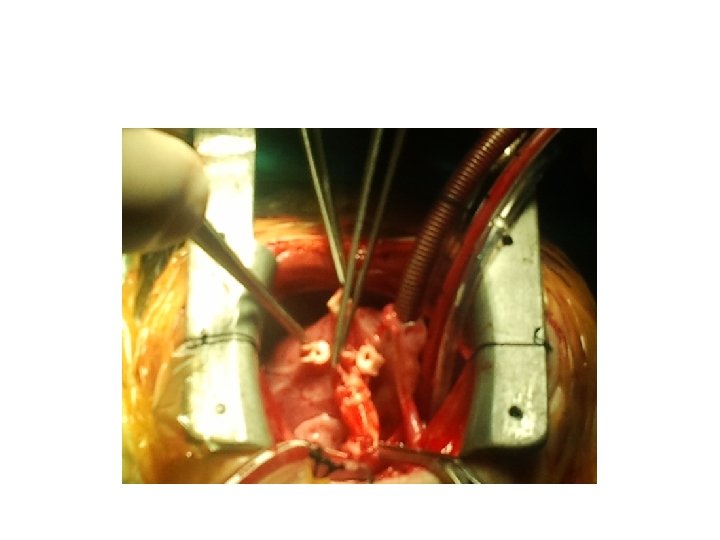

Ne yapılabilir • Kapalı kalp cerrahisi • Pda ligasyonu, shunt operasyonları, banding, • Açık

Ne yapılabilir • Kapalı kalp cerrahisi • Pda ligasyonu, shunt operasyonları, banding, • Açık kalp cerrahisi • Pompa kullanıldığı durumlar